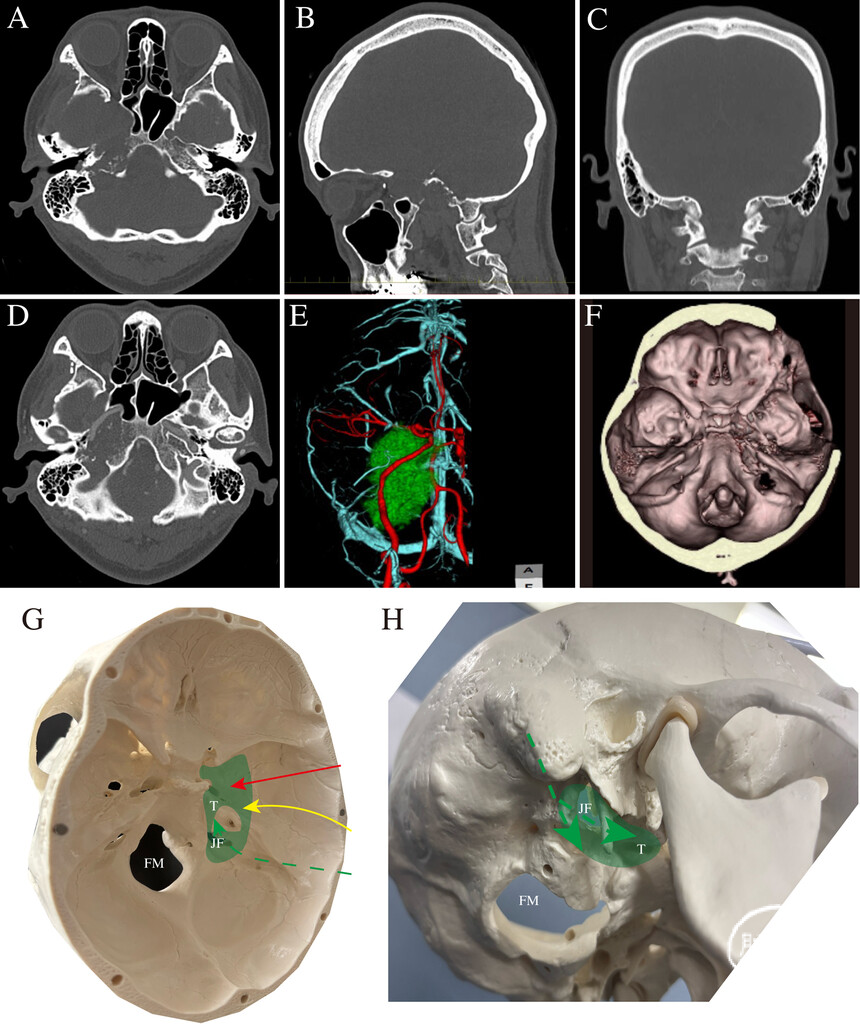

图3:A-C:术前非增强CT图像,示广泛骨质破坏。D:术前增强CT图像,示颈内动脉岩段被肿瘤包绕。E:术前三维CTA,清晰显示血管与肿瘤的空间关系。F:术前三维骨重建图像,重点显示颅底骨质破坏情况。G、H:术前手术通道3D模拟模型,分别为内侧观(G)与下外侧观(H)。红色箭头:经海绵窦入路;黄色箭头:经岩骨前入路;绿色箭头:乙状窦前入路、迷路下入路、经颈静脉孔入路及髁窝入路。FM=枕骨大孔;JF=颈静脉孔;T=肿瘤。

1.术前准备:由于WHO 1级软骨肉瘤对放疗相对不敏感,肿瘤呈广泛多腔隙、跨颅外生长,因此治疗目标为最大限度安全切除。术前已放置腰大池引流管,并基于3D模拟(图3F-H)规划了多通道联合入路,包括:经海绵窦入路、经岩骨前/后入路、乙状窦前入路、迷路下入路及经颈静脉孔入路。全麻下行多模式神经电生理监测,包括:运动诱发电位、体感诱发电位、颅神经Ⅱ~Ⅻ监测、眼外肌刺激及听觉脑干反应。术中同时使用StealthStation S8神经导航系统(Medtronic)。两组颅底手术团队同步开展前路与后路手术。